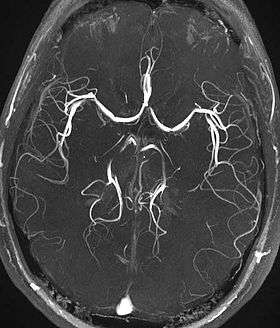

![]() Time-of-flight MRA at the level of the Circle of Willis. | |

Time-of-flight (TOF) or inflow angiography, uses a short echo time and flow compensation to make flowing blood much brighter than stationary tissue. As flowing blood enters the area being imaged it has seen a limited number of excitation pulses so it is not saturated, this gives it a much higher signal than the saturated stationary tissue. As this method is dependent on flowing blood, areas with slow flow (such as large aneurysms) or flow that is in plane of the image may not be well visualized. This is most commonly used in the head and neck and gives detailed high-resolution images.